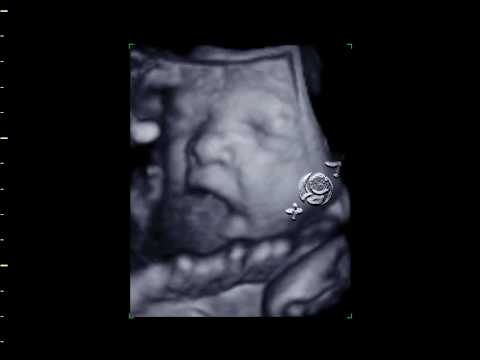

Ecografía 4D (Semana 29)